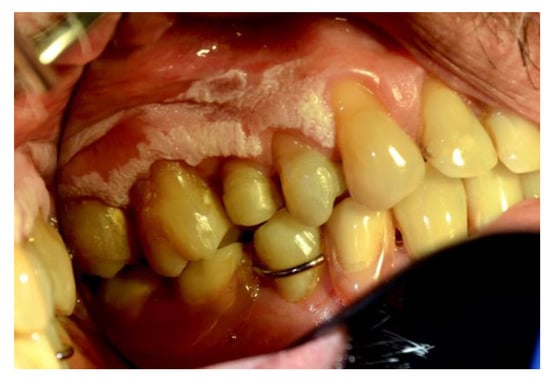

Figure 1, Figure 2, Figure 3, Figure 4, Figure 5 and Figure 6 show examples of conditions of the oral mucosa in the study groups.

Figure 3. Hyperkeratosis.

Ijerph 20 00835 g003